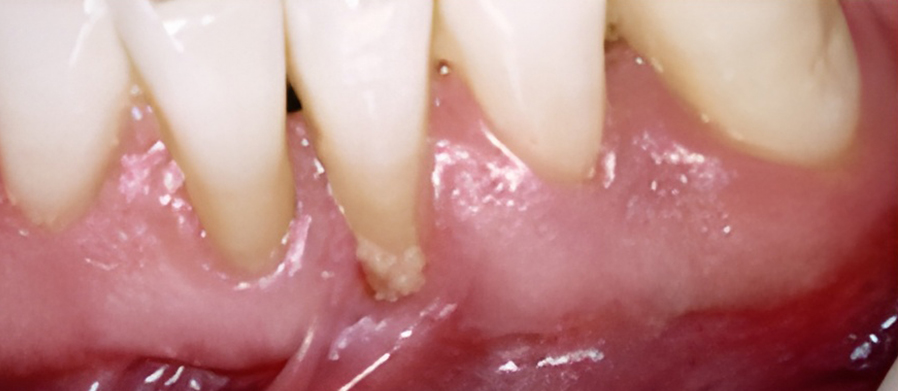

If you have signs of unhealthy gums such as redness, swelling, bleeding, tenderness, and bad breath, our doctor may recommend root planing and curettage. Root planing and curettage smooth the root surfaces beneath the gum line to remove plaque and calculus, and remove inflamed tissue so that healthy gum tissue may heal next to the cleaned and smooth tooth surface.

Because this procedure goes deeper than regular teeth cleaning, local anesthetic is needed to numb the gum.

Two office visits are usually required to complete the procedure.

The primary cause of periodontal disease is the accumulation of bacterial plaque at and under the gum line.

If plaque is not removed daily through brushing and flossing, the bacteria will cause the gum tissue to become red and swollen. At this first stage, gingivitis can and may be reversed by visiting your dentist and dental hygienist, along with your efforts at maintaining good dental hygiene.

If gingivitis is left untreated, the plaque can spread to the roots, causing an infection and damage to the supporting bone and soft tissue. The gums may separate from the tooth and start to recede. A pocket can form below the gum line and trap plaque and food. As periodontitis progresses, up to one-third of the bone can be lost.